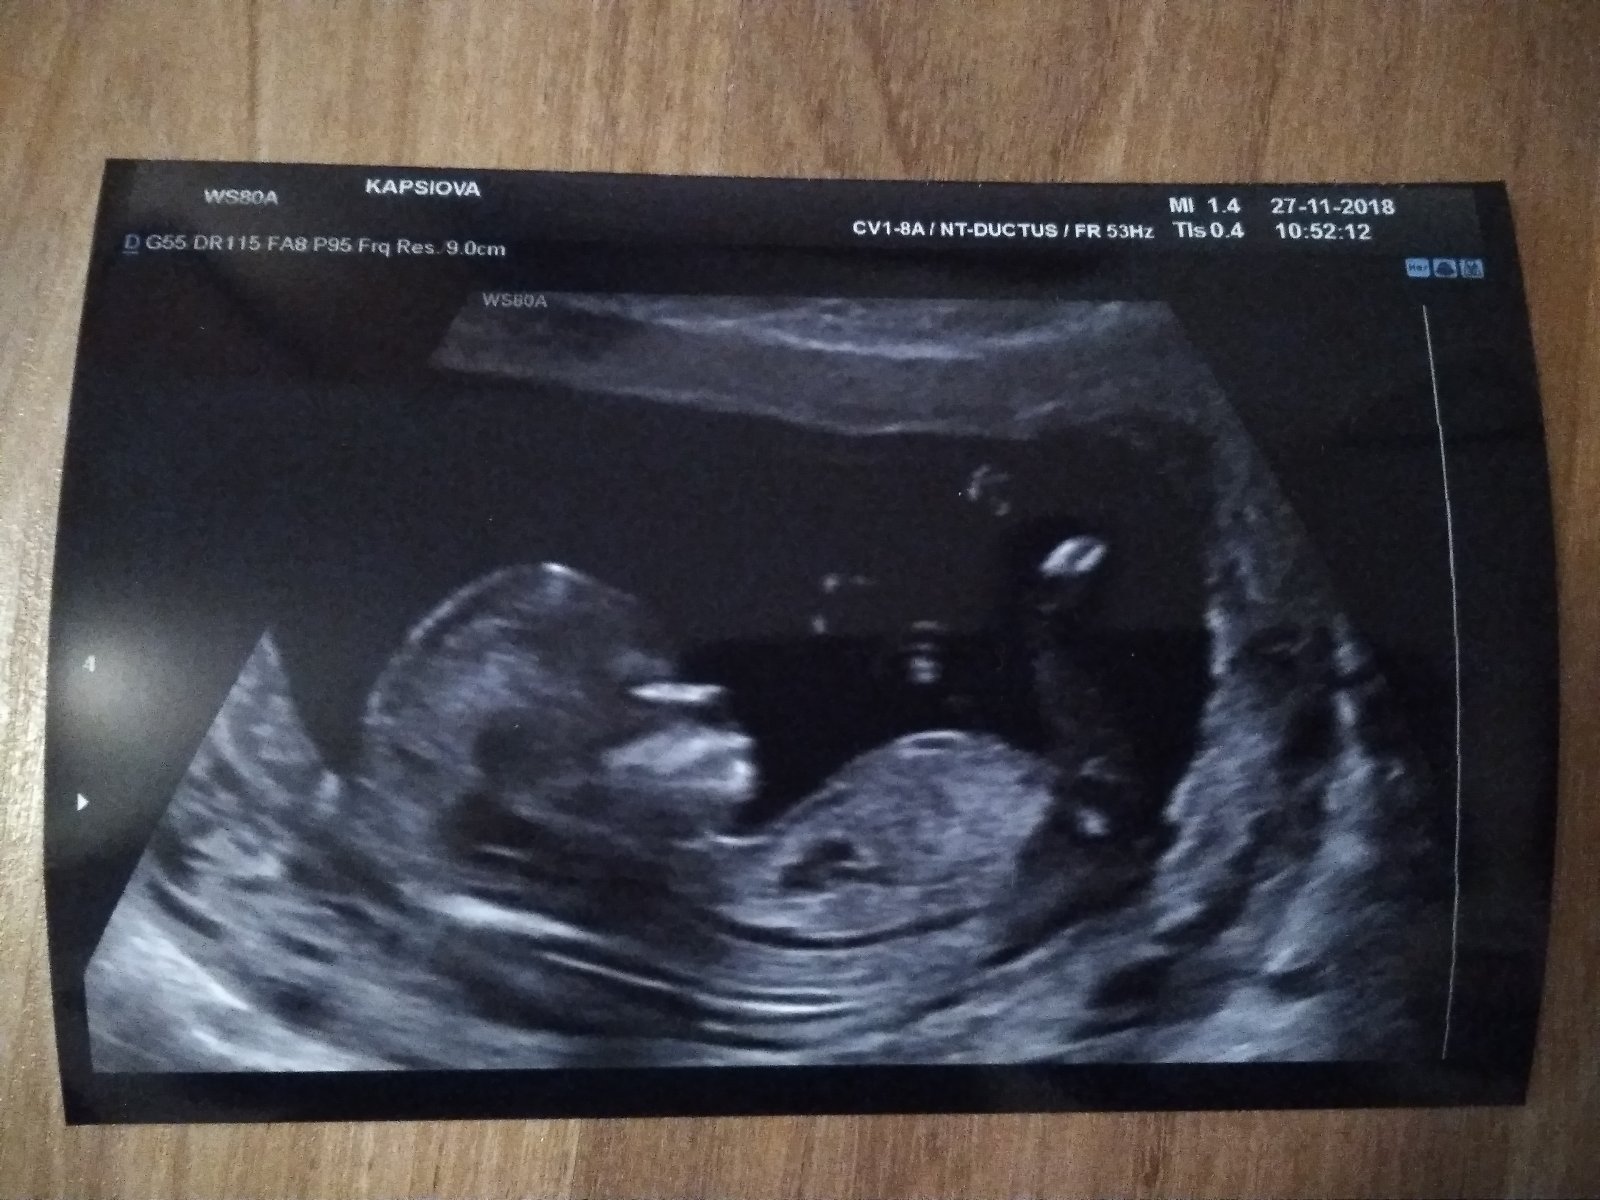

Právě začínám 23. tt. Neuvěřitelné. Miminko se zdá v pořádku, má skoro půl kila a už je děsně roztomilé. Potvrzeno z 2. screeningu, že ke dvěma chlapečkům nám přibude třetí. No tak když jsem se naučila všechny značky aut a názvy stavebních strojů, tak to aspoň využiju. Já jsem teda taková ta hodně holčičí holka, takže já bych si holčičku fakt užila, ale pro rodinný rozpočet je to každopádně dobře, utratila bych určitě majlant za různé růžovosti 🙂. Mimochodem u prvního dítěte mi pohlaví bylo jedno, takže jsem měla prostor naslouchat intuici a ta mi jasně říkala kluka. Takže komu je to fuk, možná to vycítíte. Komu to fuk není, tak nic, to přání vám překáží vnímat to, jak to je. (U druhého jsem tušila zase kluka, ale hodně jsem si přála holku, tak jsem pořád doufala.)